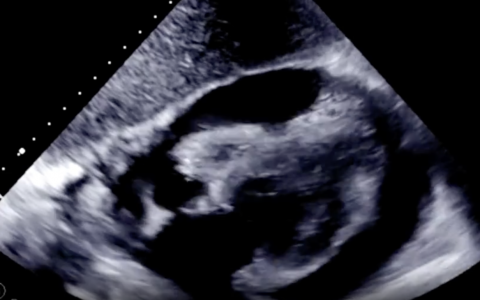

该患者表现出Wilson病的几个典型特征。Wilson病是一种遗传性疾病,由机体铜结合蛋白铜蓝蛋白的绝对生成减少引起,其特征是基底神经节胶质细胞变性(产生帕金森样症状)、血浆铜水平升高、凯-弗莱舍环(角膜铜沉积)、小结节性肝硬化和神经精神症状。